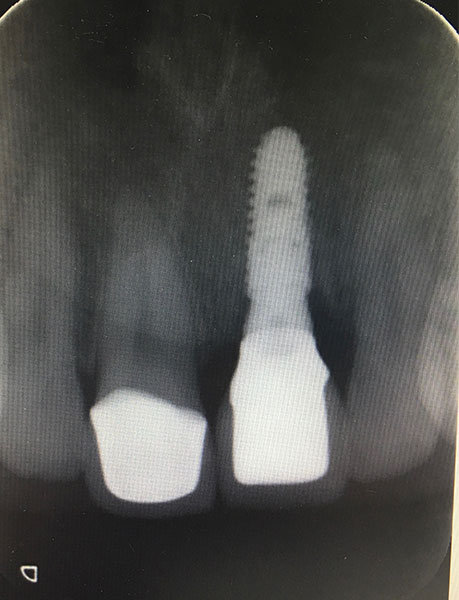

X照片植牙完成